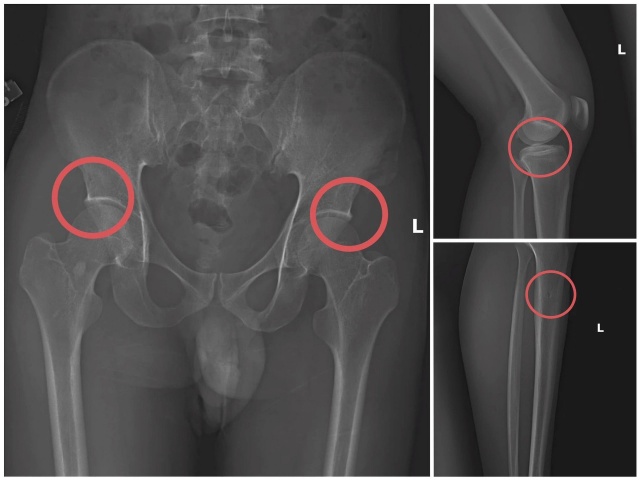

xương 6s

Bản phim chụp XQ một số tổn thương xương do đối tượng tạo ra.